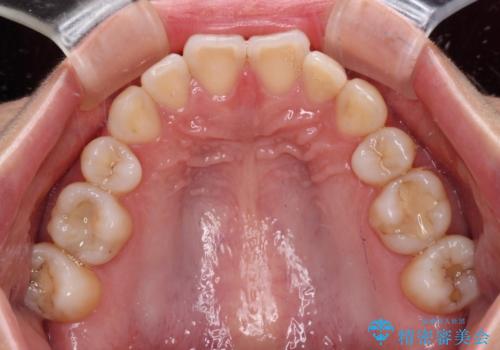

- 前歯に痛みを感じて来院された患者様です。

以前虫歯治療を行った歯が痛み出し、鼻の下を押すと強い痛みを感じていました。

根管治療を行い、その後オールセラミッククラウンにて補綴治療を行うこととしました。